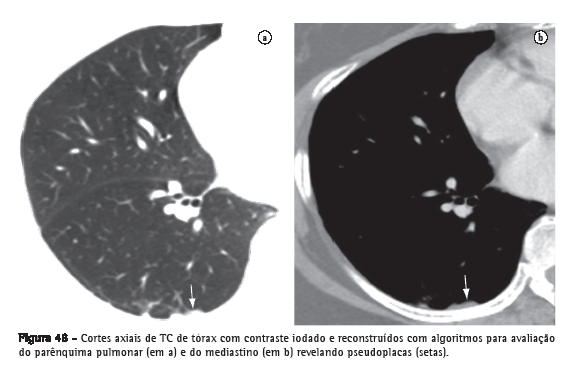

Pseudoplaca

Opacidade pulmonar periférica, adjacente à pleura visceral, formada por pequenos nódulos pulmonares coalescentes que simulam placa pleural (Figura 48).(73) Mais comumente encontrada na sarcoidose, silicose e pneumoconiose dos mineradores de carvão.